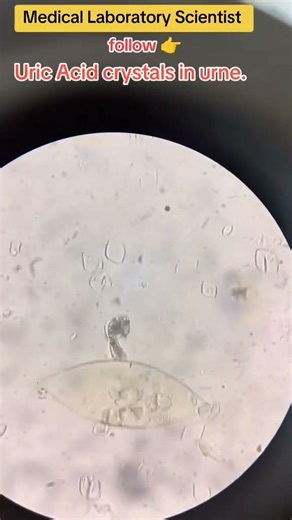

uric acid crystals in urine.#urine #microbiology #hematology #medi

…

YouTube

Medical Laboratory Scientist